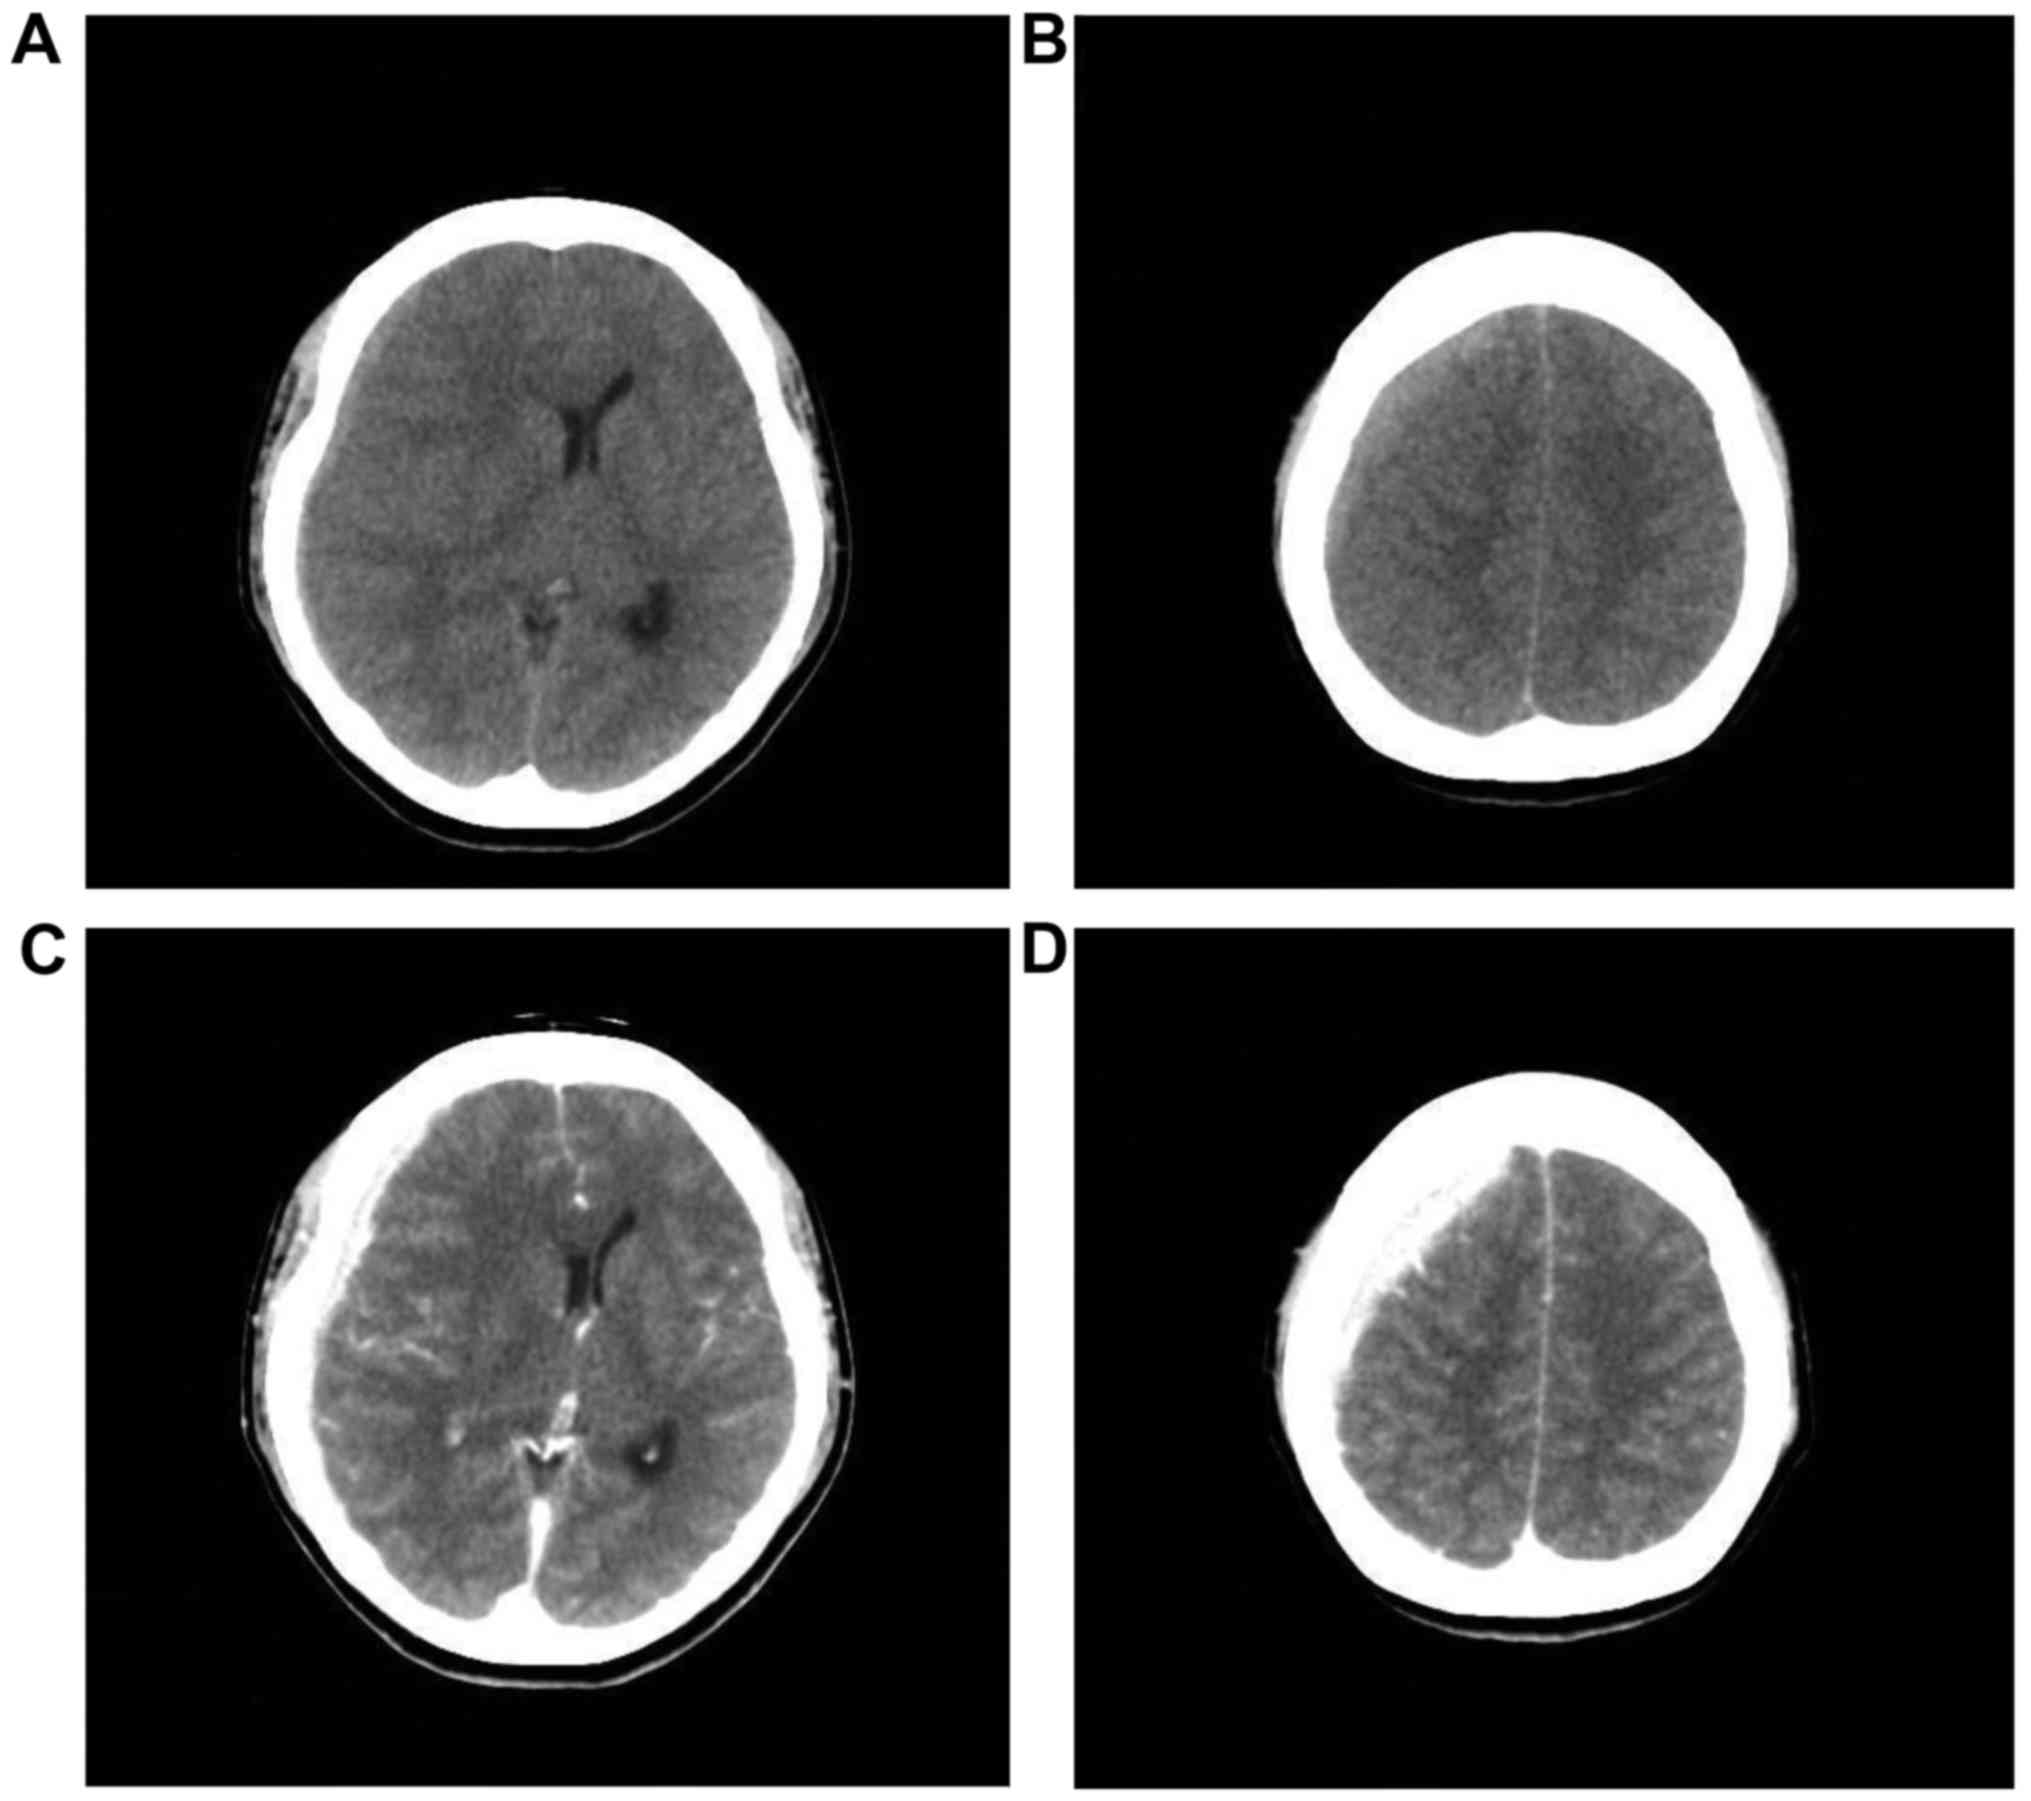

Widespread subdural metastasis from breast cancer progressing rapidly with cerebral herniation: A case report

We herein present the case of a 49‑year‑old female patient presenting with nausea and headache. The patient's medical history included breast cancer with bone and lymph node metastasis. Computed tomography (CT) examination revealed a high‑density lesion in the right subdural space, suggesting hematoma. During surgery planned for subdural hematoma drainage, an en plaque subdural yellowish‑white tumor was identified, without hematoma. Histopathological examination revealed metastatic breast cancer. The patient was administered predonisolone and her neurological symptoms gradually recovered. However, 12 days after the first operation, the clinical course was complicated by vomiting and rapid loss of consciousness. Emergency CT revealed that the subdural tumor had enlarged and decompression was performed as life‑saving surgery. However, the patient's condition progressively deteriorated and she finally succumbed to the disease 2 months after the second operation. The aim of this study was to present the case of a patient with a large en plaque subdural tumor mimicking subdural hematoma and causing rapid loss of consciousness and cerebral herniation.

Figure 1

Figure 2